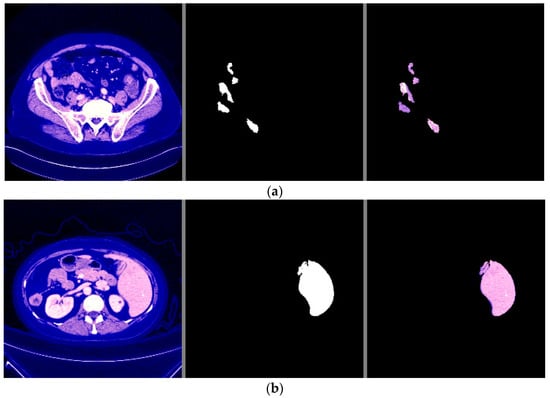

Through these functions, the model was trained on the training sample and then checked its results through the aforementioned test sample, which improved the values of the hidden coefficients for the last layer in the model in order to match the images to be trained in each phase. This process was repeated for all training phases, and in phases 15 and above, it was noticed that this accuracy did not improve more than a certain threshold, meaning that every time the model was trained on a set of images from the training sample, it checked images in the validation sample and obtained a certain accuracy. In this case, the accuracy reached 0.995, meaning that the accuracy of the model during the training and validation phases was 99.5%. The visual examples of the results of the model for detecting liver cancer from the dataset are shown in Figure 12.

Figure 12.

The visual results of the first model for cancer detection on 3D-IRCADb-01 test set: (a) normal case (no tumor detection); (b) abnormal case (tumor detection).

From the previous results mentioned in Section 3, it was observed that the first proposed method (the combination of DeeplapV3 and ResNet 50) achieved better accuracies than the second method (the combination of VGG-16, ResNet 50 V2, U-Net and LSTM) using both datasets. Therefore, we confirmed the first method to be our method. We also observed from the results that the first method obtained a high accuracy of 99.5% on small data (the case of the second dataset), which makes it more robust and efficient than other previous deep learning methods. In addition, when using the first dataset, as shown in Figure 7, it was observed that the first model could accurately detect cancer from the normal image. However, we can see from Figure 9 that the second model made some noise when detecting cancer from a normal image (as shown in Figure 9a). In terms of the second dataset (small data), we can observe from Figure 12 and Figure 16 that, when detecting cancer from the image, the two models detected cancer with some noise, but the first model was still better than the second model, with less noise. We employed the ReLU activation function in our models because it does not become active in all neurons at the same time. In addition, ReLU gives the highest accuracy, compared with other nonlinear activation functions, such as the Tanh activation function. Table 5 shows a performance comparison when using ReLU as an activation function and other nonlinear activation functions on the 3D-IRCADb-01 dataset.